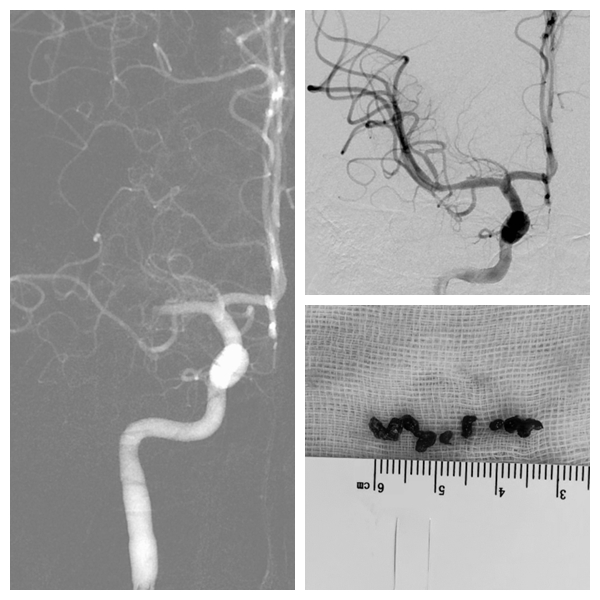

经急诊颅脑CT、核磁共振、头颈部CTA等检查,提示患者右侧大脑中动脉M1段闭塞。急诊医生紧急联系神经介入值班医生进行会诊。神经外科主任医师陈寒春结合检查结果,初步判断为急性脑梗死,立即启动脑卒中绿色通道。

经神经内科会诊,先予静脉溶栓;溶栓后经评估,患者存在桥接取栓的必要。陈寒春及其团队综合分析病情,讨论、评估后,确认患者有“急诊动脉取栓术”指征。于是,便联系手术室、麻醉科等做好各项术前准备,同时与家属进行术前沟通。在取得家属同意后,立即为患者进行急诊取栓。

术中,陈寒春凭借精湛的技术,与多学科紧密合作,利用抽吸导管,将数枚暗红色的血栓从脑动脉中成功取出,被堵塞的血管即刻再通,抽吸开通过程约5分钟。